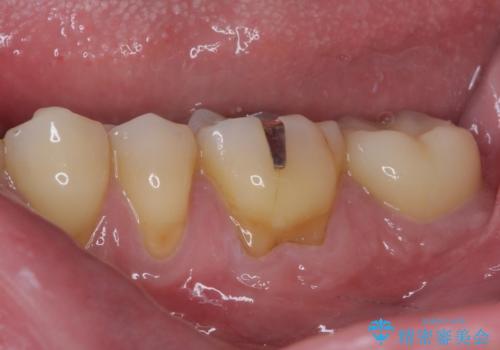

後方は歯肉内にまで虫歯が及んでいたため、歯肉の一部を切除して、クラウンとの境目を明示して処置を行いました。

クラウン装着後には、来院時に気になさっていた歯肉の腫れが解決され、快適に生活を送れるようになりました。